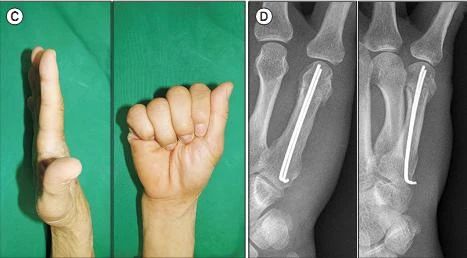

На снимке выше представлен случай смещенной антеградной интрамедуллярной фиксации перелома шейки пятой пястной кости правой руки.

(А) Рентгенологическое исследование перед операцией показывает: угол дорсально-шейной части пястной кости, сопровождающийся укорочением;

(B) Интраоперационная рентгеноскопическая рентгенограмма;

(В) Внешний вид движения мизинца через 2 недели после операции;

(D) Рентгенограмма через 8 недель после операции (из ссылки 6)